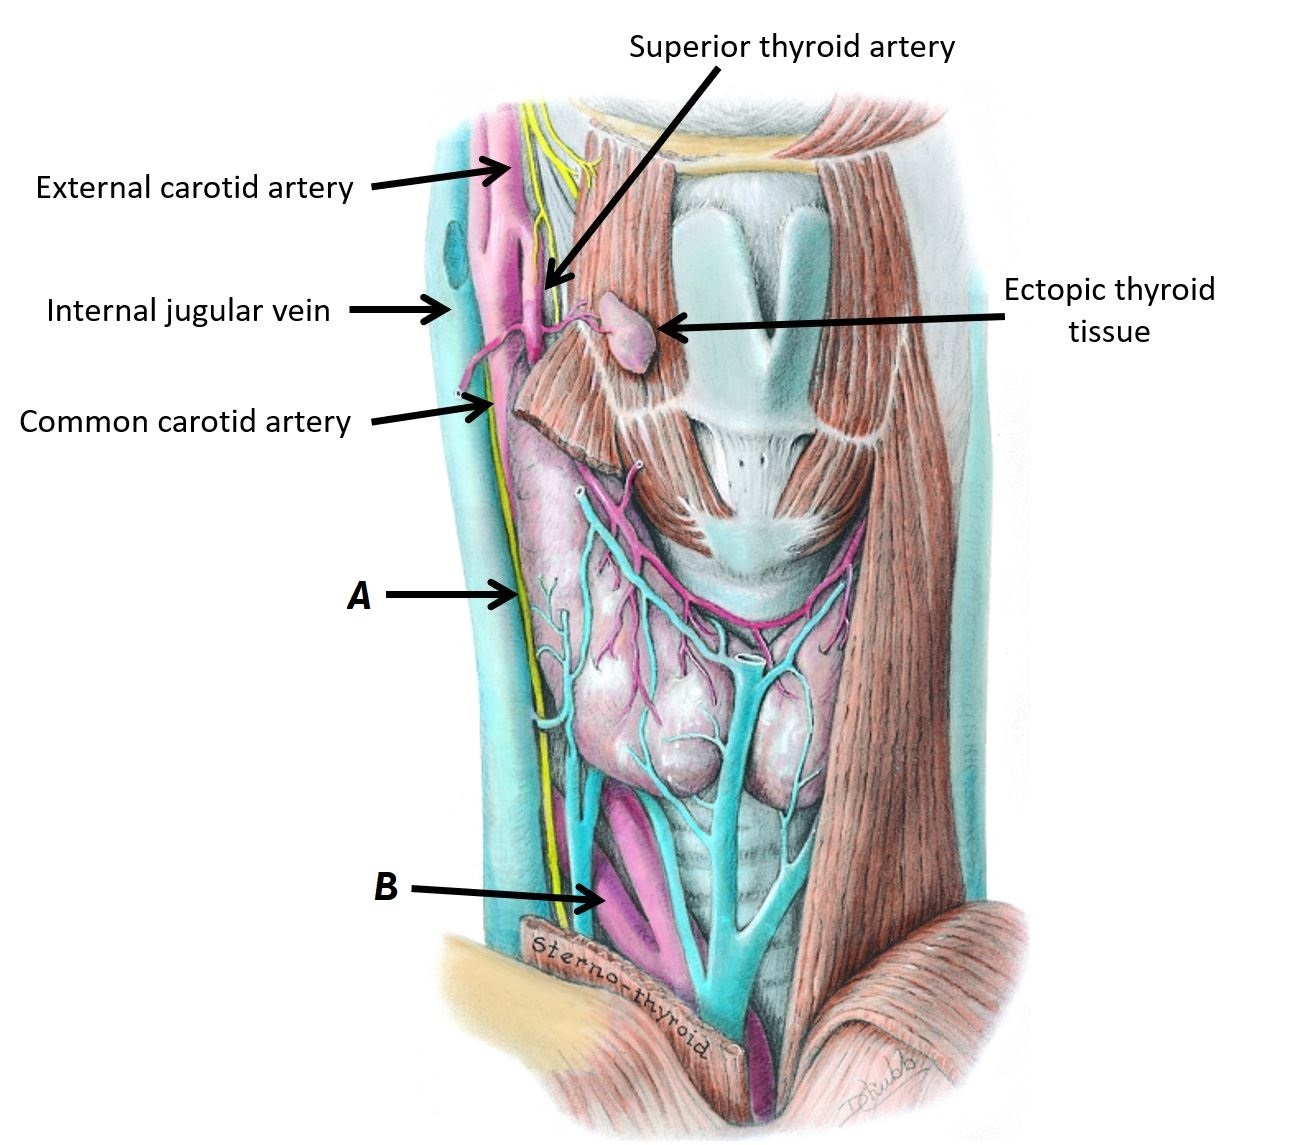

Name structures A, B and C

A - Right vagus nerve

B - Recurrent laryngeal nerves

C - Parathyroid gland